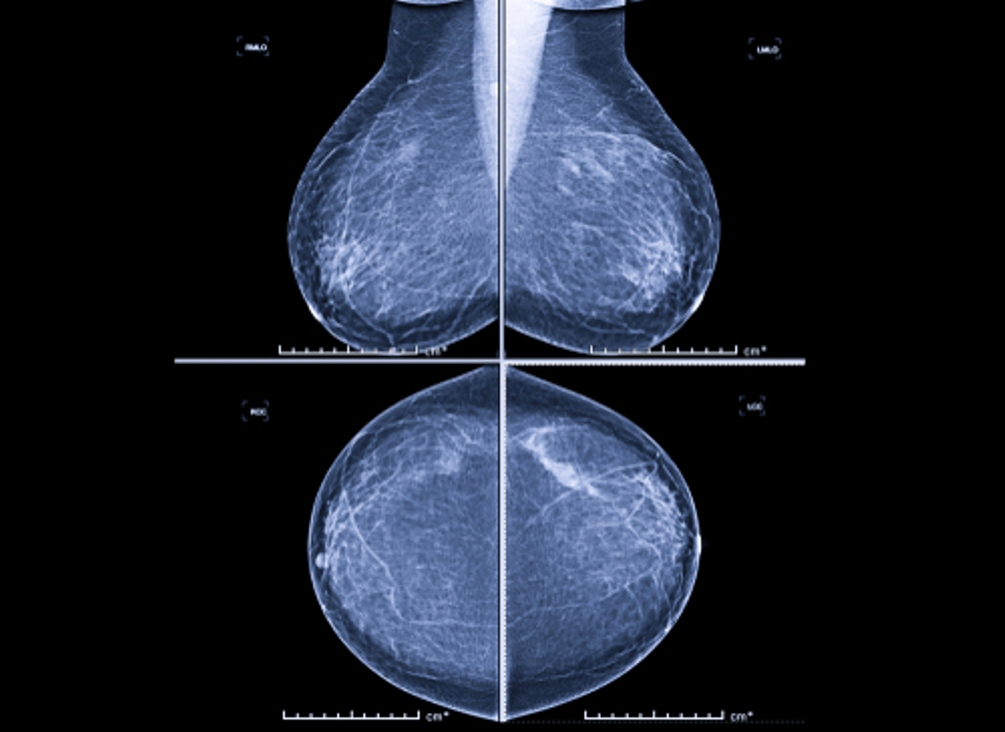

„Mikrokalcifikáty môžu byť v úplne skorom štádiu viditeľné len na mamografii, často ide o zmeny veľké len niekoľko milimetrov. Práve preto je mamografické vyšetrenie také dôležité a nenahraditeľné. Väčšie zmeny môžu byť neskôr viditeľné aj na ultrazvuku,“

vysvetľuje MUDr. Alexandra Bieliková, lekárka rádiológie AGEL Mammacentra sv. Agáty.

Nový bioptický stôl má výrazne väčšie zorné pole, čo umožňuje presnejšie zameranie aj drobných lézií. Automatizované funkcie zároveň zjednodušujú pracovné postupy zdravotníckeho personálu a znižujú riziko manuálnych chýb. Technológia poskytuje lekárom 360-stupňový prístup k prsníku, čo je výhodné najmä pri ťažšie dostupných nálezoch, a zároveň zvyšuje komfort pacientiek počas samotného zákroku.